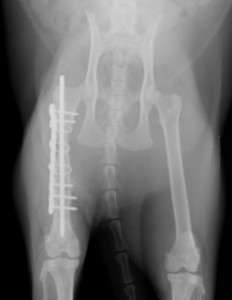

手術前 手術後

プレートロッド(ロッキングプレート&髄内ピン)にて整復しました。